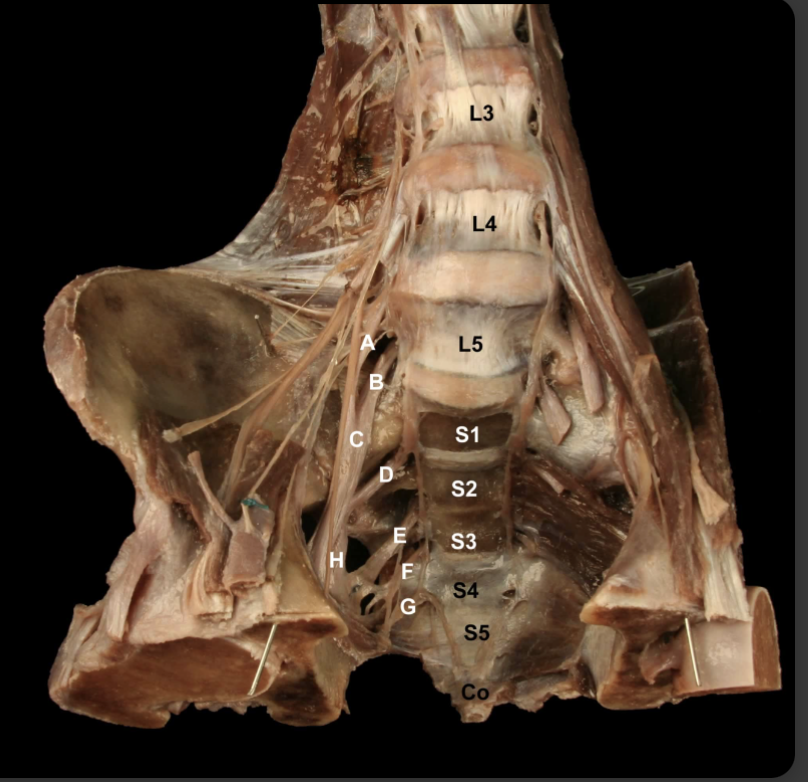

<p><strong>&nbsp;</strong></p><p>Identify the Nerves and their corresponding nerve levels indicated on this <strong>Anterior view</strong> of the Pelvis:<strong> Sacral Plexus</strong></p>

Identify the Nerves and their corresponding nerve levels indicated on this Anterior view of the Pelvis: Sacral Plexus

A. L4 Nerve Root

B: L5 Nerve Root

C: Lumbosacral Trunk (L4-L5)

D: S1 Nerve Root

E: S2 Nerve Root

F: S3 Nerve Root

G: S4 Nerve Root

H: Sciatic n. (L4-S3)